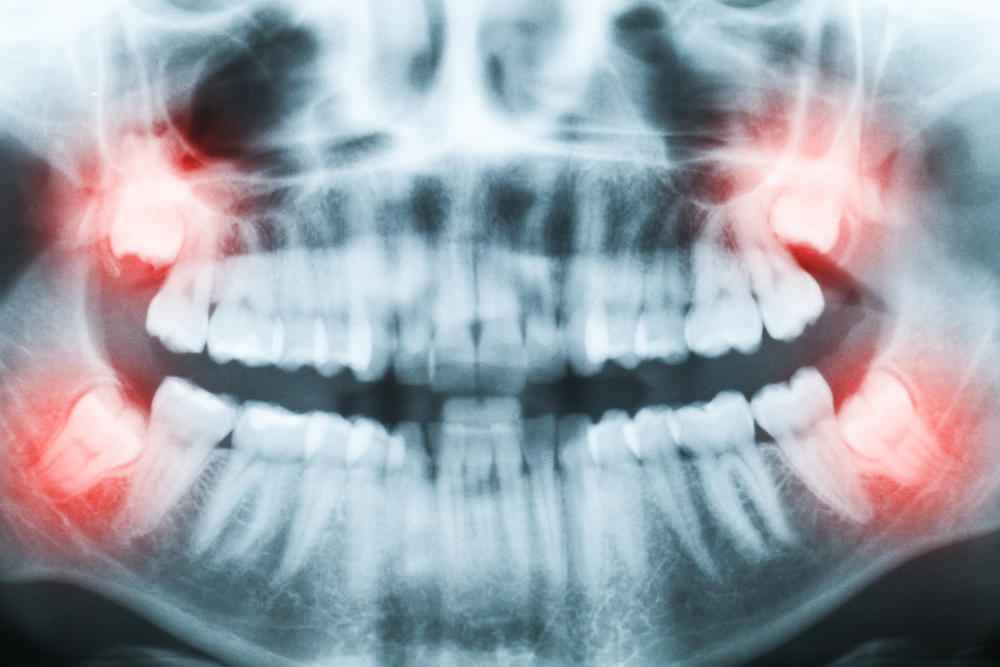

З усіх наявних у людини 32 зубів, зуби мудрості найбільш складні. Це 4 крайніх зуби, якими з обох сторін закінчуються обидва зубних ряди.

Їх головна складність полягає в тому, що свій ріст вони починають досить пізно (від 18 до 28 років), коли організм, включаючи щелепу, повністю сформований. У зв’язку з цим, прорізування зубів мудрості нерідко супроводжується болісними відчуттями, а іноді вимагає хірургічного втручання. Однак буває і так, що до зрілого віку зуби мудрості залишаються в яснах, хоча при цьому вони сформовані.

Оскільки зуб мудрості є замикаючим в зубному ряду і лише з одного боку до нього примикає сусідній зуб, напрямок його зростання може бути непередбачуваним. В результаті може розвиватися дистопія — відхилення зуба від звичайного положення по відношенню до всього зубного ряду. Найчастіше такі зуби ростуть в сторону, завдаючи незручностей і травмуючи щоку або язик. Це вносить дискомфорт в повсякденне життя, заважаючи пережовувати їжу і навіть розмовляти. В цьому випадку зуб мудрості необхідно видалити, щоб позбавити себе від мук.

Ще одним показанням до видалення зуба мудрості є його ураження карієсом. Повноцінно вилікувати такий зуб дуже проблематично, оскільки корені мають, як правило, складну форму: можуть бути закручені в вузол і рости в різних напрямках. Це перешкоджає їх якісному пломбуванню, а тому немає сенсу рятувати зуб, який продовжить псуватися і може дати ускладнення.